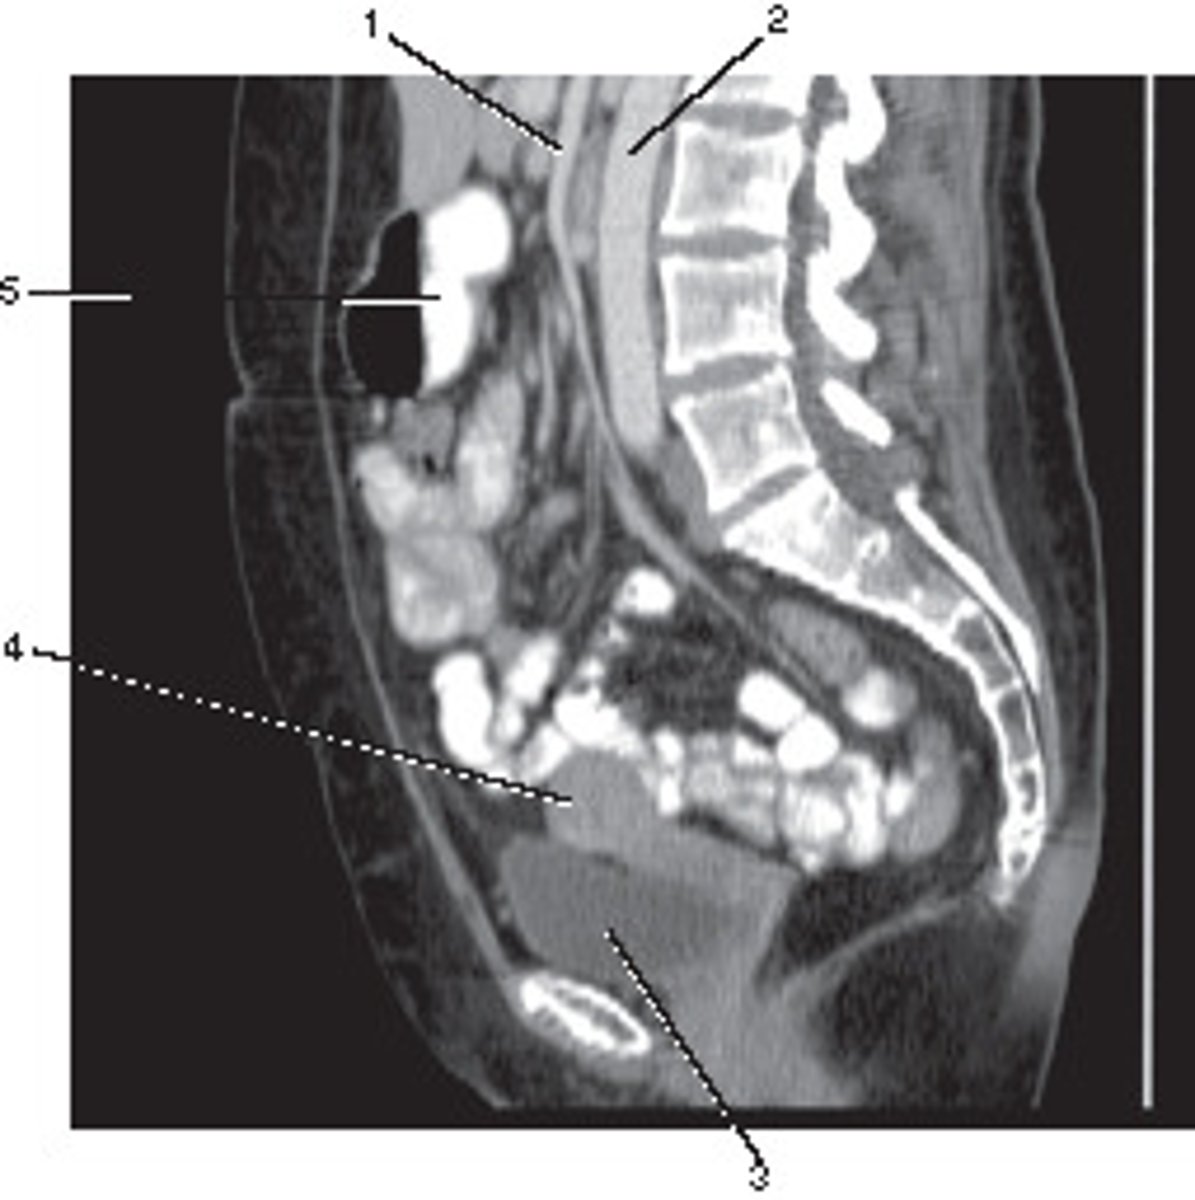

Sagittal

<p>What anatomic plane best describes this image</p>

Number 1 corresponds to which of the following?

<p>Number 1 corresponds to which of the following?</p>

Stomach

Number 2 corresponds to which of the following?

Ileum

34